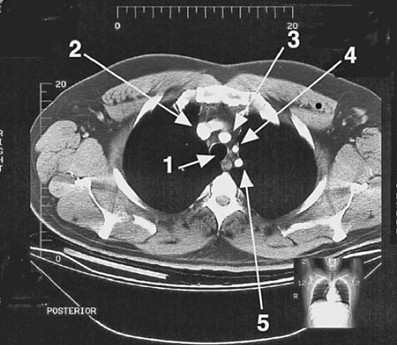

A 65-year-old male patient develops neurological symptoms due to an embolus in the left common carotid artery. In the CT scan in following figure, the involved vessel is indicated by which of the following arrows?

Arrow 4 points to the left common carotid artery. The three arteries arising from the arch of the aorta are lined anteriorly to posteriorly on a slanted line: arrow 3 (choice C) shows the brachiocephalic artery, arrow 4 (choice D) points to the left common carotid artery, and arrow 5 (choice E) indicates the left subclavian artery. Arrow 2 (choice B) points to the right brachiocephalic vein, which is joined here by the left brachiocephalic vein. Arrow 1 (choice A) points to the trachea, which is filled with air and thus is not radiopaque.